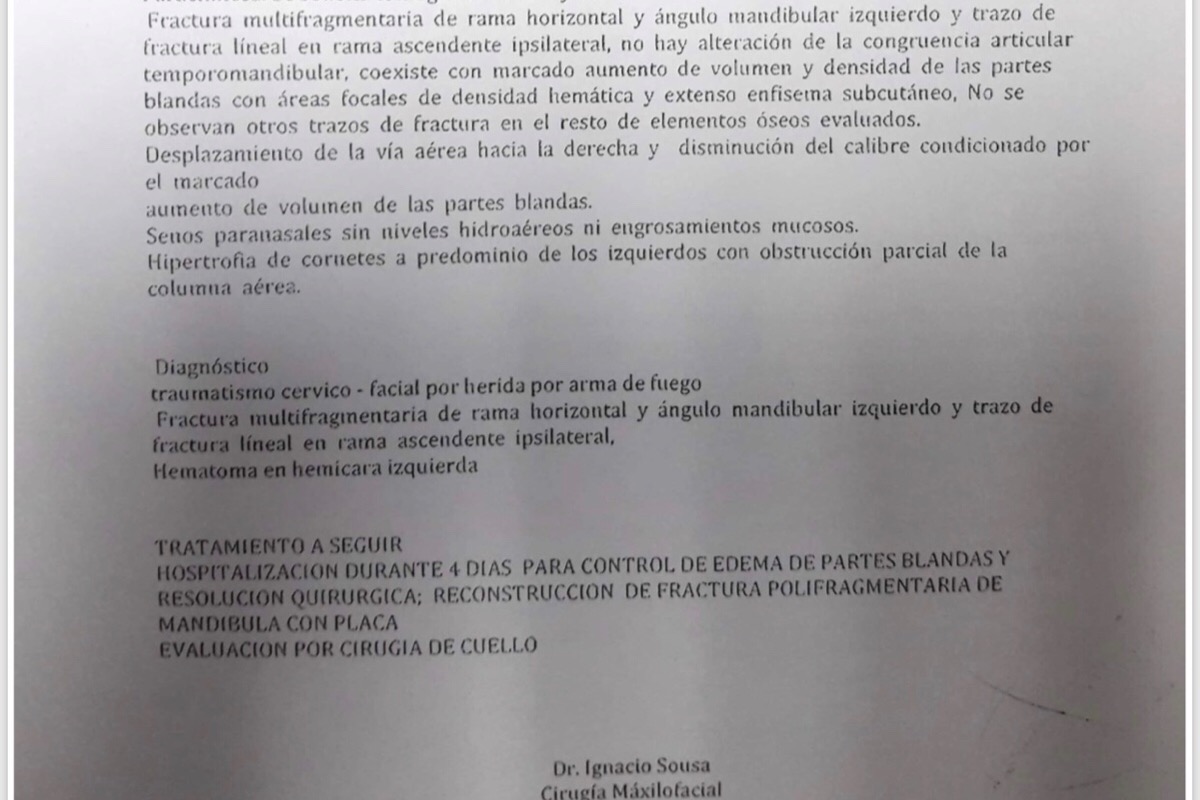

Vive en Caracas, exactamente en Residencias La California, el Marqués. Saliendo a trabajar, este 26 de diciembre. Ricardo se encontró con 2 sujetos en la planta baja de su edificio. Ellos quisieron agarrarlo y hacerlo subir a su apartamento para robarlo y robar a toda su familia. Como se opuso a dicha acción, le DISPARARON en la cara, a la altura de la mandíbula.

Adjuntas las fotos del suceso, cuentas medicas, y otras documentaciones que respaldan el suceso.

Vive en Caracas, exactamente en Residencias La California, el Marqués. Saliendo a trabajar, este 26 de diciembre. Ricardo se encontró con 2 sujetos en la planta baja de su edificio. Ellos quisieron agarrarlo y hacerlo subir a su apartamento para robarlo y robar a toda su familia. Como se opuso a dicha acción, le DISPARARON en la cara, a la altura de la mandíbula.

Adjuntas las fotos del suceso, cuentas medicas, y otras documentaciones que respaldan el suceso.